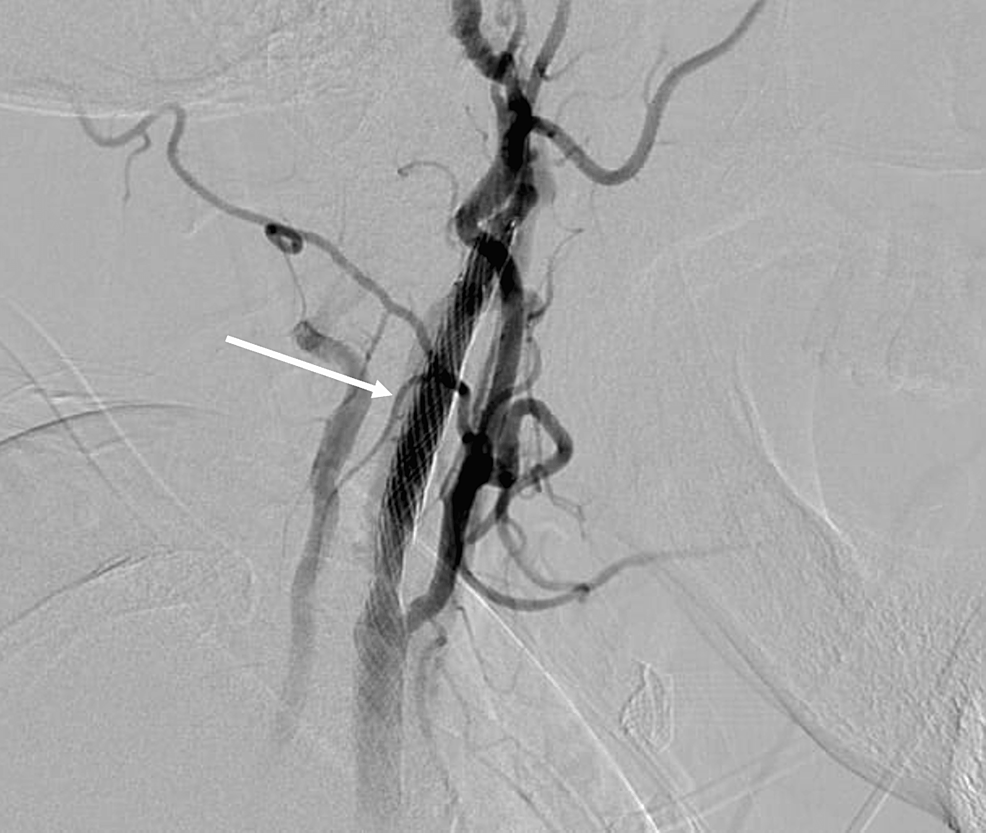

From www.cureus.com

Hand Knob Syndrome Secondary to Ipsilateral Carotid Fibromuscular Dysplasia and What Is A Hand Knob Stroke Left hand weakness and sensory deficit. — cortical ischemic stroke affecting the precentral “hand knob” area is a rare but well known stroke entity. — clinical manifestation: — hand knob stroke is a rare stroke with a good prognosis and a low stroke recurrence rate. This anatomic landmark is responsible for intricate control of hand motor movements. What Is A Hand Knob Stroke.

Hand Knob Syndrome Secondary to Ipsilateral Carotid Fibromuscular Dysplasia and What Is A Hand Knob Stroke — cortical ischemic stroke affecting the precentral “hand knob” area is a rare but well known stroke entity. — clinical manifestation: — hand knob stroke is a rare stroke with a good prognosis and a low stroke recurrence rate. Left hand weakness and sensory deficit. This anatomic landmark is responsible for intricate control of hand motor movements. What Is A Hand Knob Stroke.